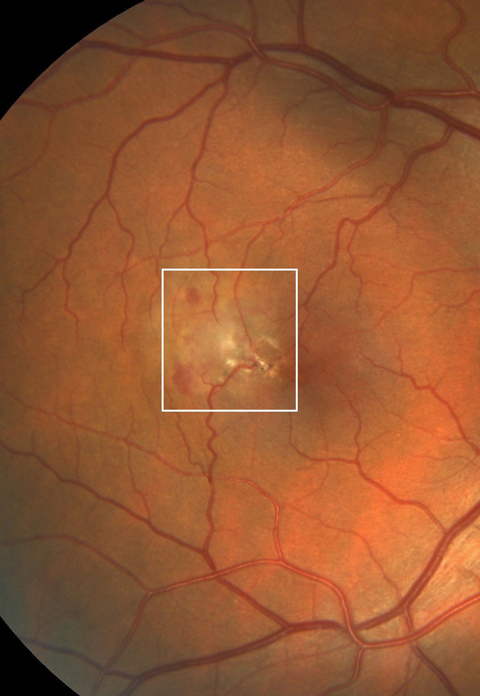

Macular telangiectasia type 2 complicated with choroidal neovascularization